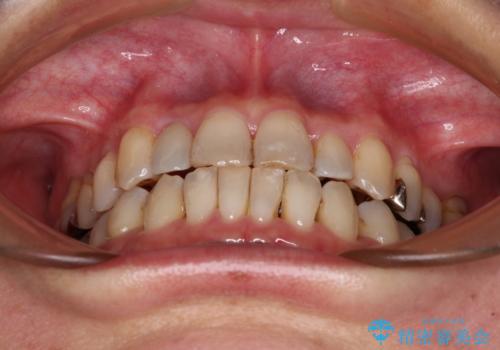

急速拡大装置 前歯の反対咬合をインビザラインで改善

上顎骨の幅が下顎骨よりも小さいので、拡大装置により骨幅を広げて上下関係を改善すると同時にワイヤー矯正で反対咬合の改善を図り、その後インビザラインにて歯並びを整えることとしました。

上顎前歯の矮小歯は矯正治療の途中でオールセラミッククラウンを装着し、左右のバランスを整えることとしました。

急速拡大装置の使用により奥歯の咬み合わせが劇的に変わり、その変化を利用して反対咬合を改善することができました。

治療期間中は奥歯が咬み合わず、食事が取りにくいなどの不都合がありましたが、最終的にはきれいに整えることができました。